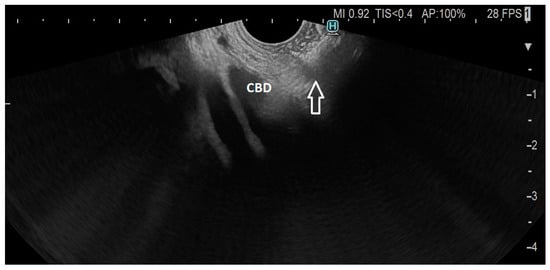

The technique of EUS-guided biliary drainage (EUS-BD) has evolved significantly over the past decade, particularly since the first clinical case of LAMS was described in 2014 [7]. In short, after the window of bile duct approach from the duodenal bulb or, less frequently, the distal stomach is identified under EUS guidance, and the cautery-enhanced device is slowly advanced into the bile duct above the level of the tumoral obstruction using pure-cut current. After penetration and proper advancement into the bile duct, the distal flange is deployed under endosonographic real-time guidance, followed by device retraction for achieving apposition of the bile duct and gastrointestinal tract, when the proximal flange of the LAMS can be safely deployed (Figure 1, Figure 2 and Figure 3). This revolutionary type of device has brought a paradigm shift in the field of interventional endoscopy, but many debates about the technical aspects of this procedure are still unresolved. We will strive to provide a pragmatic overview of the main points of contention among endoscopists performing this technique.

Figure 1. Dilated common bile duct (CBD) with EC-LAMS in the duodenum (arrow).